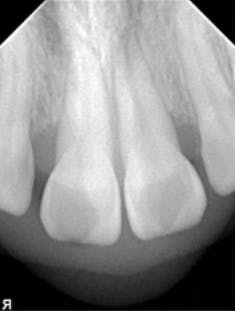

A 22-year-old female presented to a periodontal office with the chief complaint of gum swelling in the maxillary anterior (figure 2). Radiographs taken of the area showed unexpected bone loss in the maxillary central and incisor region (figure 3). The patient admitted to the dentist that she was using a technique known as gap banding that she had found out about online to close the spaces between her front teeth. She stated that she would use these bands at night while she slept, and one morning one of the bands was gone. A few months later, she developed the "swelling in her gums."

The periodontist surgically exposed the area and, after debridement, noticed an orthodontic rubber band encapsulated with fibrous tissue at the alveolar crest of Nos. 8 and 9 (figure 4). The band was then removed (figure 5) and the area was grafted.